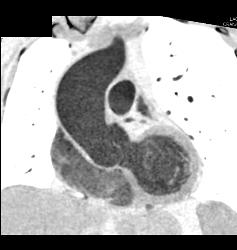

SVC Occlusion With Collaterals. SVC Occlusion Was Due to Tumor